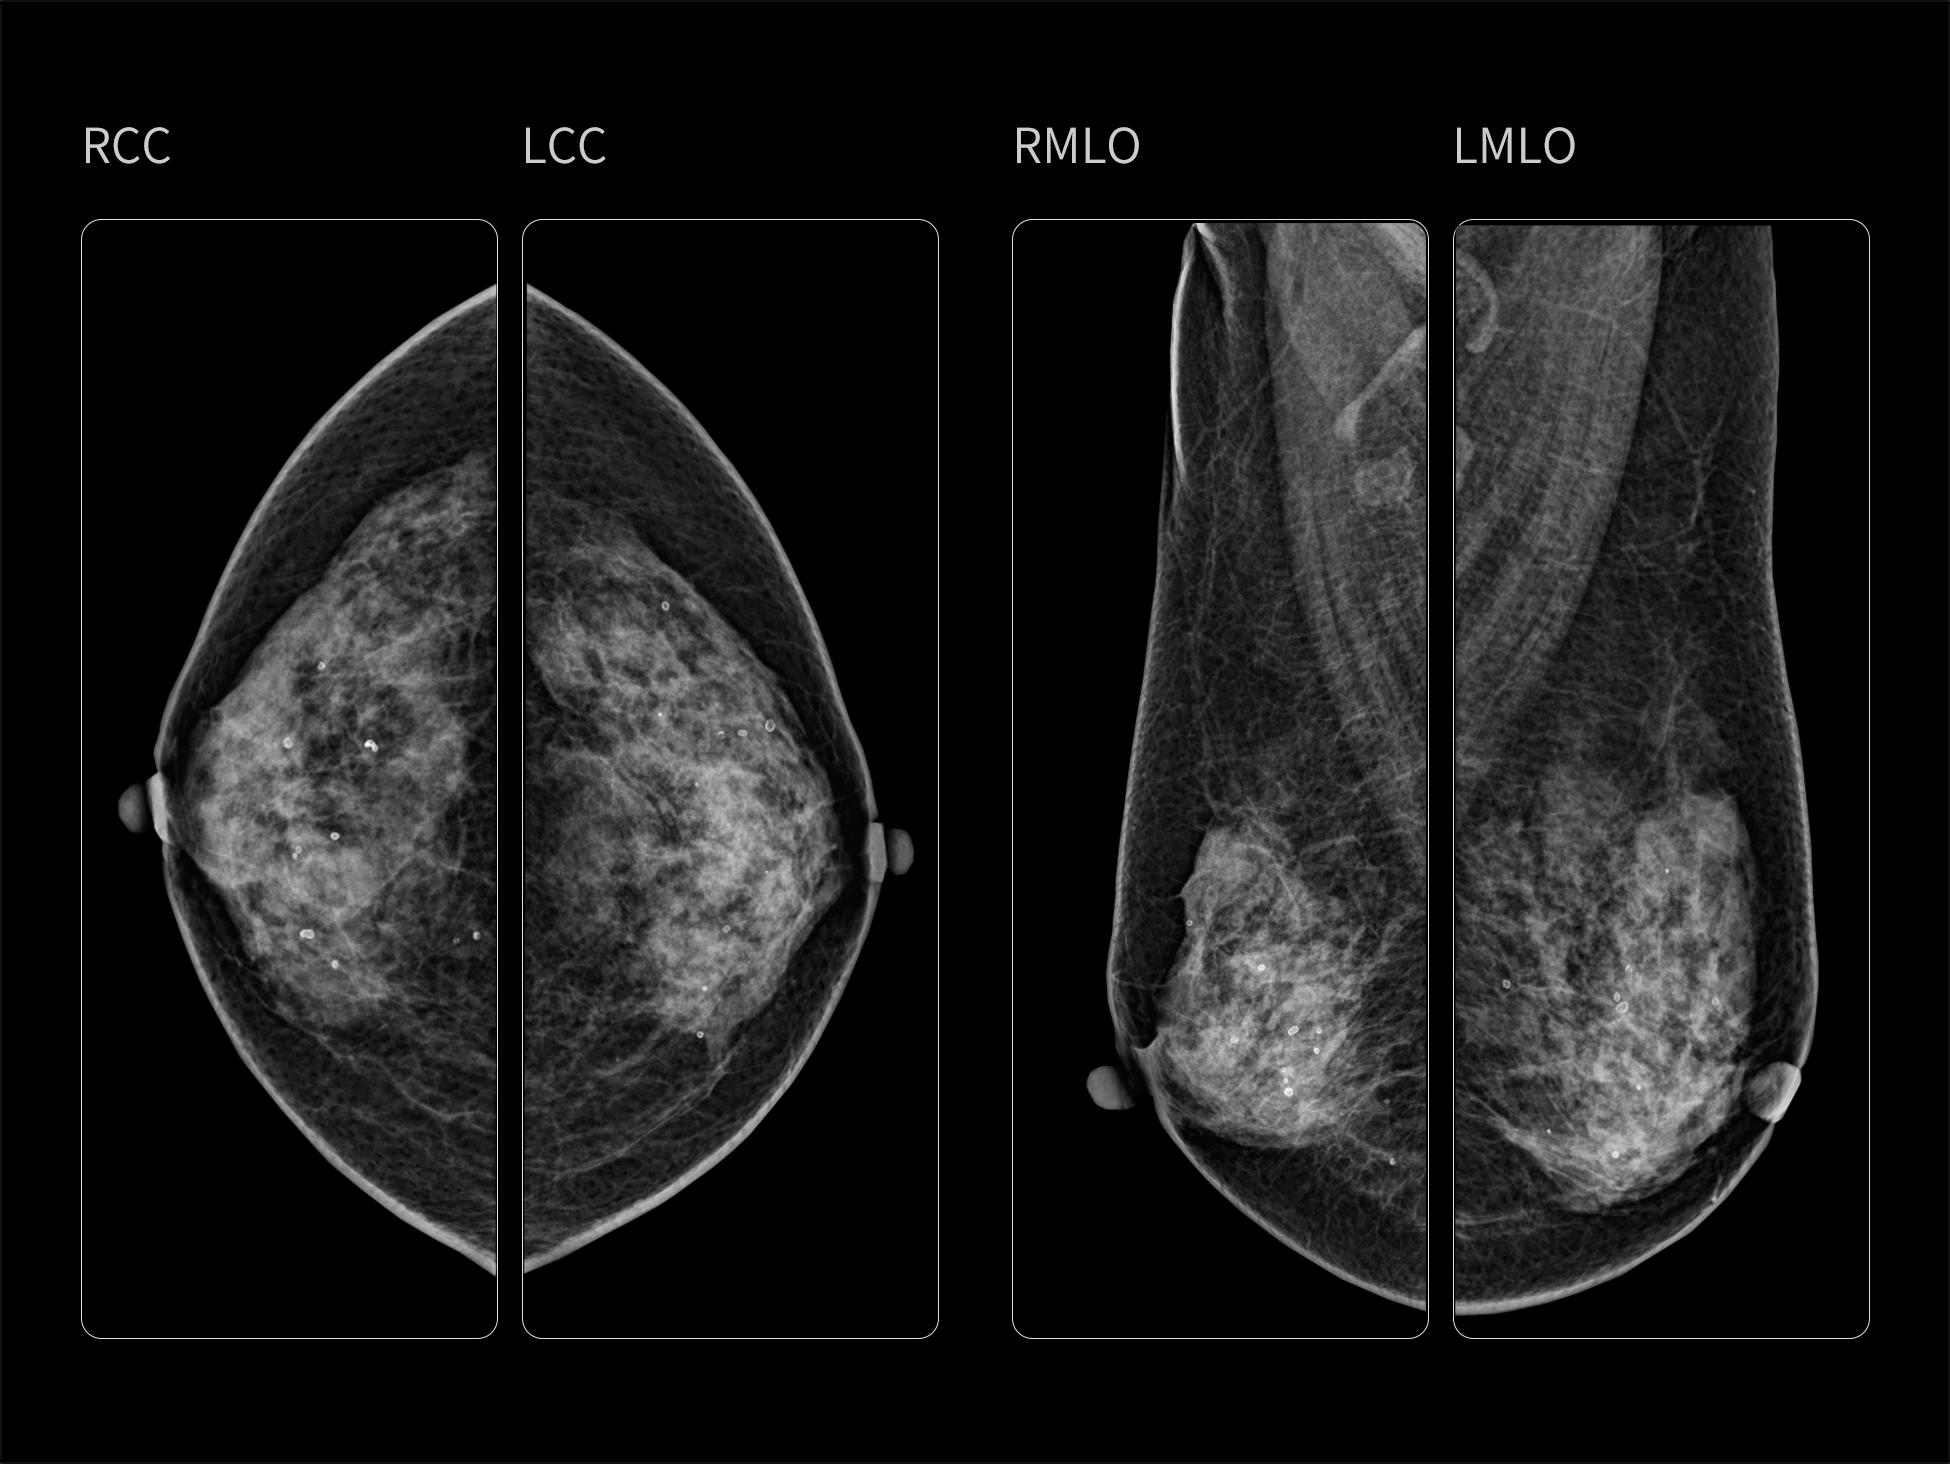

- Optimized System with An Outstanding Image Chain